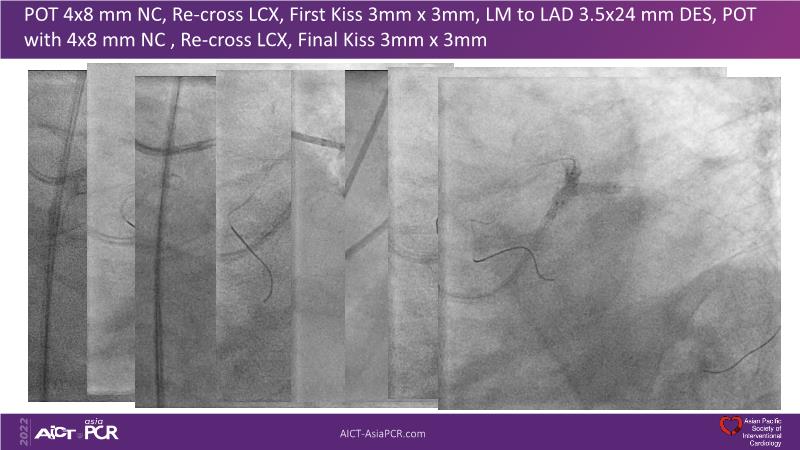

In this session, presenters describe how to use IVUS and physiology in the assessment of left anterior descending and/or left circumflex ostium in distal left main disease. Discover in the second part the general principles and clinically validated strategies for ultralow contrast coronary angiography and zero contrast percutaneous coronary intervention.

- To learn how imaging can help with strategising left main PCI, plaque preparation, device sizing and optimising results